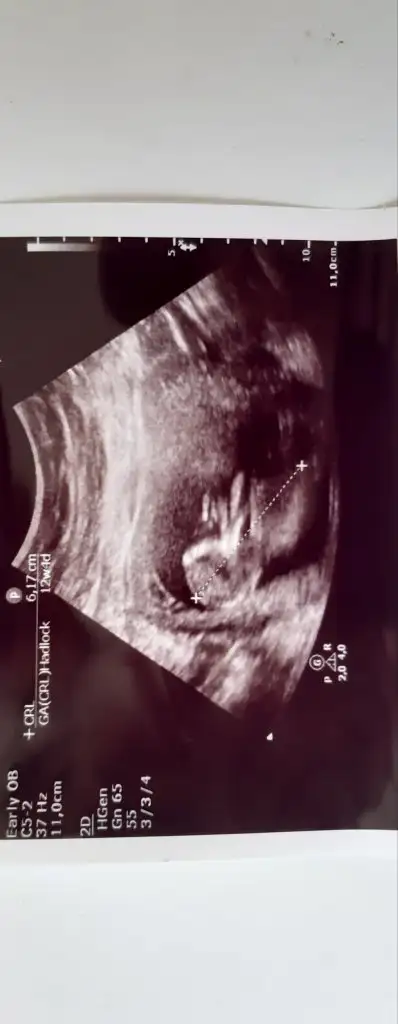

ÖgrendinizmiEvet net bulamadım en net resmi bu doktor net çekmemiş aslında 12 haftalık teşekkür ederim

Kaç haftalık usg sanki erkek gibi eminde olmadım 11 12 13 haft usgler olmalı tekrar usg paylaşınMerhabalar tahmininizi çok merak ediyorum :)

Üçlü taramada büyük ihtimalle kız olduğu söylendiNet degil usg tek tek çekermisiniz usgler yada başka usg olursa paylaşın 12-13 haftalarda olabilir şimdilik eminde değilim kız gibi gibi emin değilim tekrar usg paylaşın